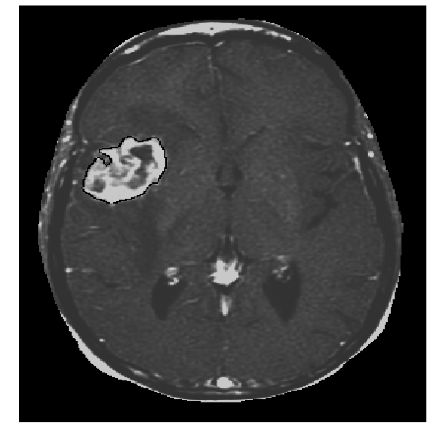

下面是我的硕士论文【6】中采用水平集方法分割出的肿瘤,就是白色那一块。这个方法的数学味有点浓,考虑到咱们是闲聊,就不摆公式了,毕竟后面还有很多事。